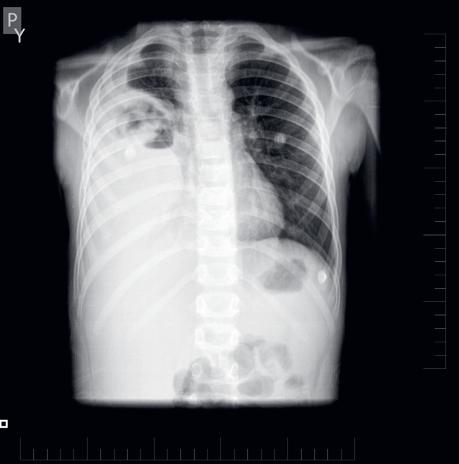

60 Akútne respiračné zlyhanie

MUDr. Ivana Gondová, PhD.